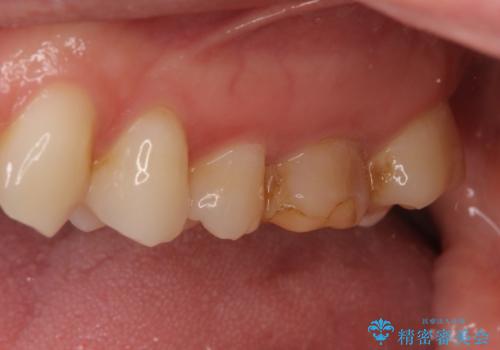

- 他院で自費根管治療、矯正治療、セラミック治療をする予定でしたが、根管治療終了後から忙しく通わなくなり放置していました。

海外転勤が決まったため、それまでに治療をしてほしいとご来院されました。(矯正治療はせずにセラミック治療のみ)

海外転勤が決まり、急いでセラミック治療をしてほしいとご来院された患者様です。

根管治療に症状がなく、上の歯に関しては土台もそのまま使用可能であったため、下の歯の土台、上下の歯のセラミック治療を行いました。